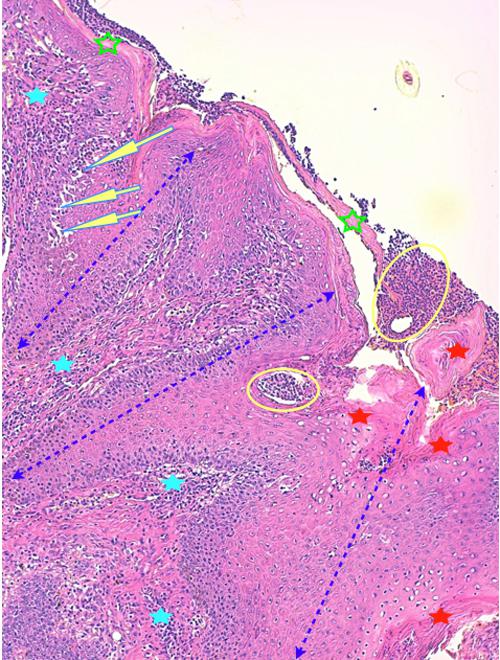

Photo 3 (Hémalun-Eosine X100) peau velue : Les infundibula folliculaires sont le siège d’une acanthose irrégulière et d’une hyperkératose (avec alternance d’ortho et de parakératose). Leur abouchement est souvent obstrué d’un matériel pustuleux. Leur gaine épithéliale externe présente des lignes de fissuration et de lyse des attaches desmosomiales des cellules épithéliales, dans lesquelles s’immiscent des granulocytes.

Légendes de la Photo 3 :

- Double flèche bleue pointillée : grand axe des infundibula folliculaires

- Ovales jaunes : pustules obstruant l’ostium ou l’infundibulum

- Flèches jaunes : fissuration linéaire dans la gaine épithélilae externe d’un follicule parallèle au grand axe de l’infundibulum

- Étoiles vertes évidées : hyperkératose orthokératosique

- Étoiles rouges pleines : hyperkératose parakératosique

- Étoiles turquoises pleines : infiltrat inflammatoire dermique périvasculaire à diffus

Photo 4 (Hémalun-Eosine X200) peau velue : Vue rapprochée de la Photo 3 montrant

la zone de fissuration de la gaine épithéliale externe d’un infundibula folliculaire avec lyse des

attaches desmosomiales intercellulaires et afflux de granulocytes éosinophiles donnant

naissance à des micro-pustules pariétales multiloculaires.

Légendes de la Photo 4 :

- Double flèche verte : grand axe de l’infundibulum folliculaire

- Double flèche rose : épiderme

- Flèches jaunes : fissuration de la gaine épithéliale externe avec lyse des attaches desmosomiales intercellulaires et afflux de granulocytes éosinophiles

- Ronds marrons : parakératose

- Étoiles rouges : micro-pustules pariétales multiloculaires (folliculite murale) et luminales obstruant l’abouchement folliculaire

- Étoiles turquoises : à gauche infiltrat inflammatoire dermique (au milieu en bas, erreur)

- Étoile vertes : orthokératose